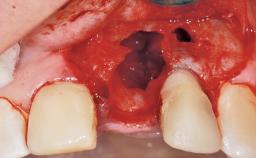

A 30-year-old female patient was referred to the office for the treatment of tooth 11. Her chief concern at the initial visit was to inquire, “Why is my tooth pink?” Upon clinical examination, it was determined that tooth 11 had a previous history of trauma and that the clinical crown had become noticeably pink in color as a result of internal resorption. This diagnosis was confirmed radiographically, indicating a large radiolucency involving the central and distal portions of the clinical crown. It was determined that restoration of this tooth was not possible, and that extraction was indicated. The presence of a mid-line diastema, which the patient wanted to reproduce, directed the treatment plan for tooth replacement utilizing a dental implant.

Placement Protocol Immediate implant placement

Tooth Site Maxillary incisor or canine

Socket Morphology Single-root socket

Socket Integrity Sufficient, with intact bone walls